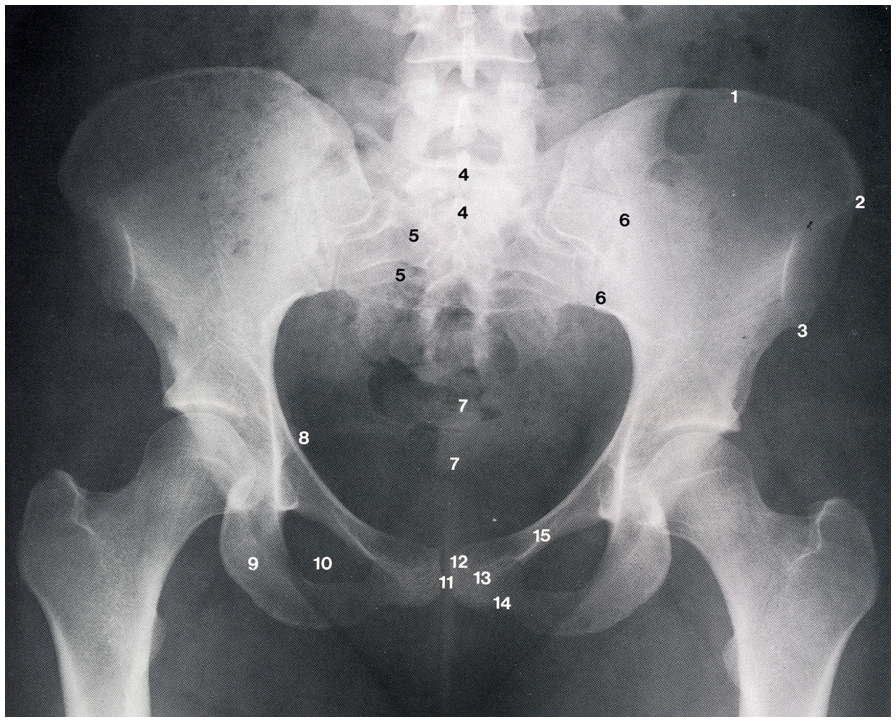

Identify 2,3,9

2 - Anterior superior iliac spine

3 - Anterior inferior iliac spine

9 - Ischial tuberosity